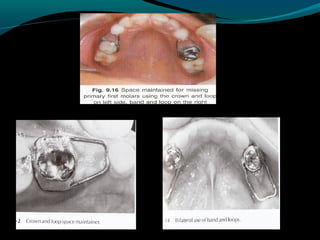

BAND & LOOP APPLIANCE

(Fixed,Non functional,Passive space

maintainer)

It is used to maintain the space of a single

tooth.

Inexpensive & easy to fabricate.

It does not restore the occlusal function of

the missing tooth.

Indications

Unilateral loss of the primary first molar

before or after eruption of the permanent

first molar.

Bilateral loss of a primary molar before the

eruption of the permanent incisors.

LINGUAL ARCH

(Fixed,Non functional,Passive

Mandibular arch appliance)

Used to maintain the posterior space in

the primary dentition.

The lingual arch is often suggested when